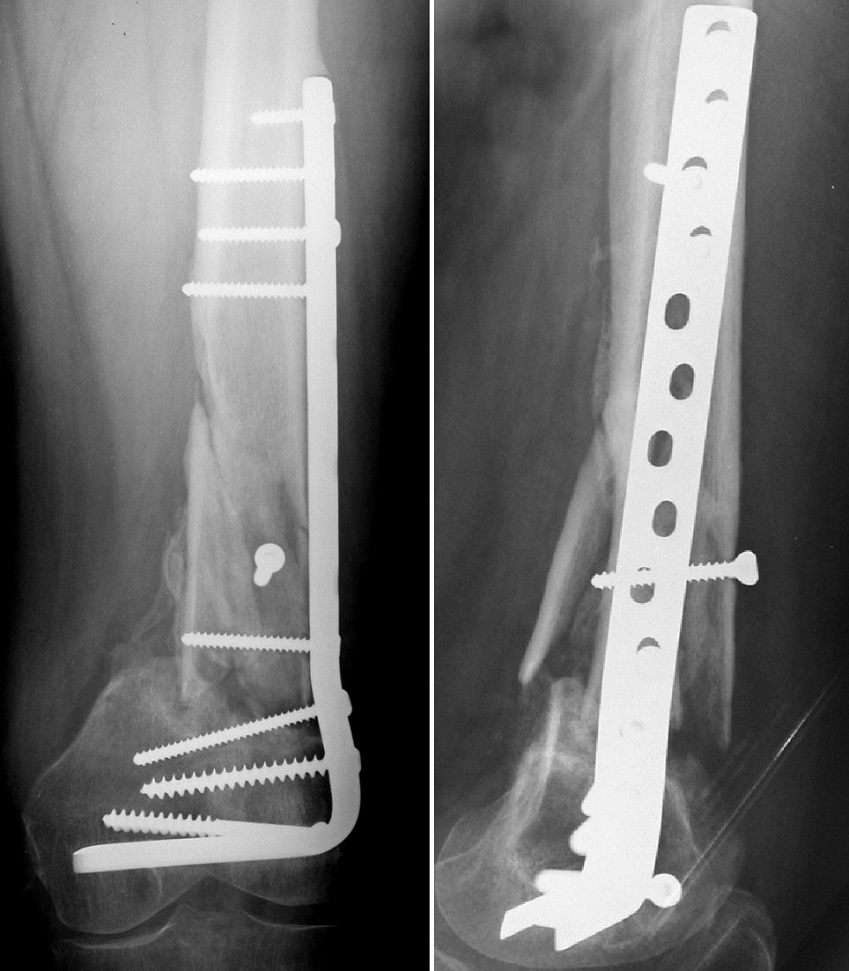

Paziente maschio, anni 74, pseudoartrosi femore distale sinistro.

Paziente maschio, anni 74, pseudoartrosi femore distale sinistro

Controllo a 3 mesi di distanza dopo osteosintesi con lama placca, innesto osseo contrapposto, cellule staminali autologhe e gel piastrinico

Controllo a 3 mesi di distanza dopo osteosintesi con lama placca, innesto osseo contrapposto, cellule staminali autologhe e gel piastrinico.